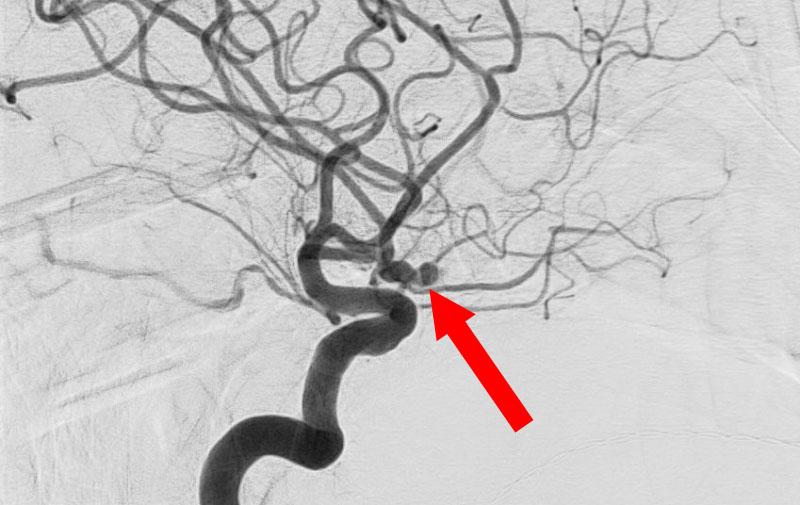

くも膜下出血

左中大脳動脈瘤破裂

40代

救急外来

No.1596 手術中